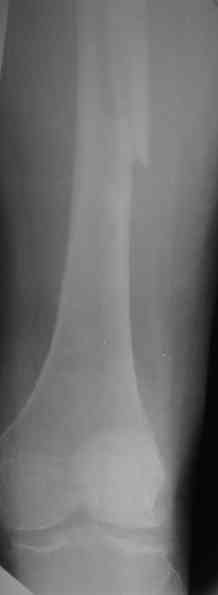

Представленные снимки неудачны ни по качеству, ни по обзорности. Классификационно предположительно Ванкувер В2. Накостный остеосинтез LCP с использованием монокортикальной фиксации в проксимальном отделе.

Представленные снимки неудачны ни по качеству, ни по обзорности.

? На фасных проекциях видно все до коленного сустава - куда ж больше обзорность? Качество IMHO совершенно обычное, приемлемое, весь перелом виден...

1. Представляющей наибольшую ценность из представленной информации следует считать фасные снимки №3и №4 (если считать по порядку). На снимке №3 не видны ни проксимальный отдел бедра с зоной (линией) перелома - наложение тени, ни дистальная зона (линия) перелома - область не захвачена. Снимок №4 демонстрирует дистальную линию перелома, но не показывает уровень конца ножки эндопротеза. В таких сучаях как способ можно выполнять снимок "с метками" - чтобы при при наложении снимков на негатоскопе иметь целостностное представление о всём сегменте от тазобедренного до коленного суставов.

1. На снимке №3 не видны ни проксимальный отдел бедра с зоной (линией) перелома

Там видно расхождение фрагментов, диастаз чуть медиальнее б. вертела.

Снимок №4 демонстрирует дистальную линию перелома, но не показывает уровень конца ножки эндопротеза.

Кончик ножки виден на самом верху этого снимка.

Вот фрагменты этих снимков с более различимыми областями интереса.